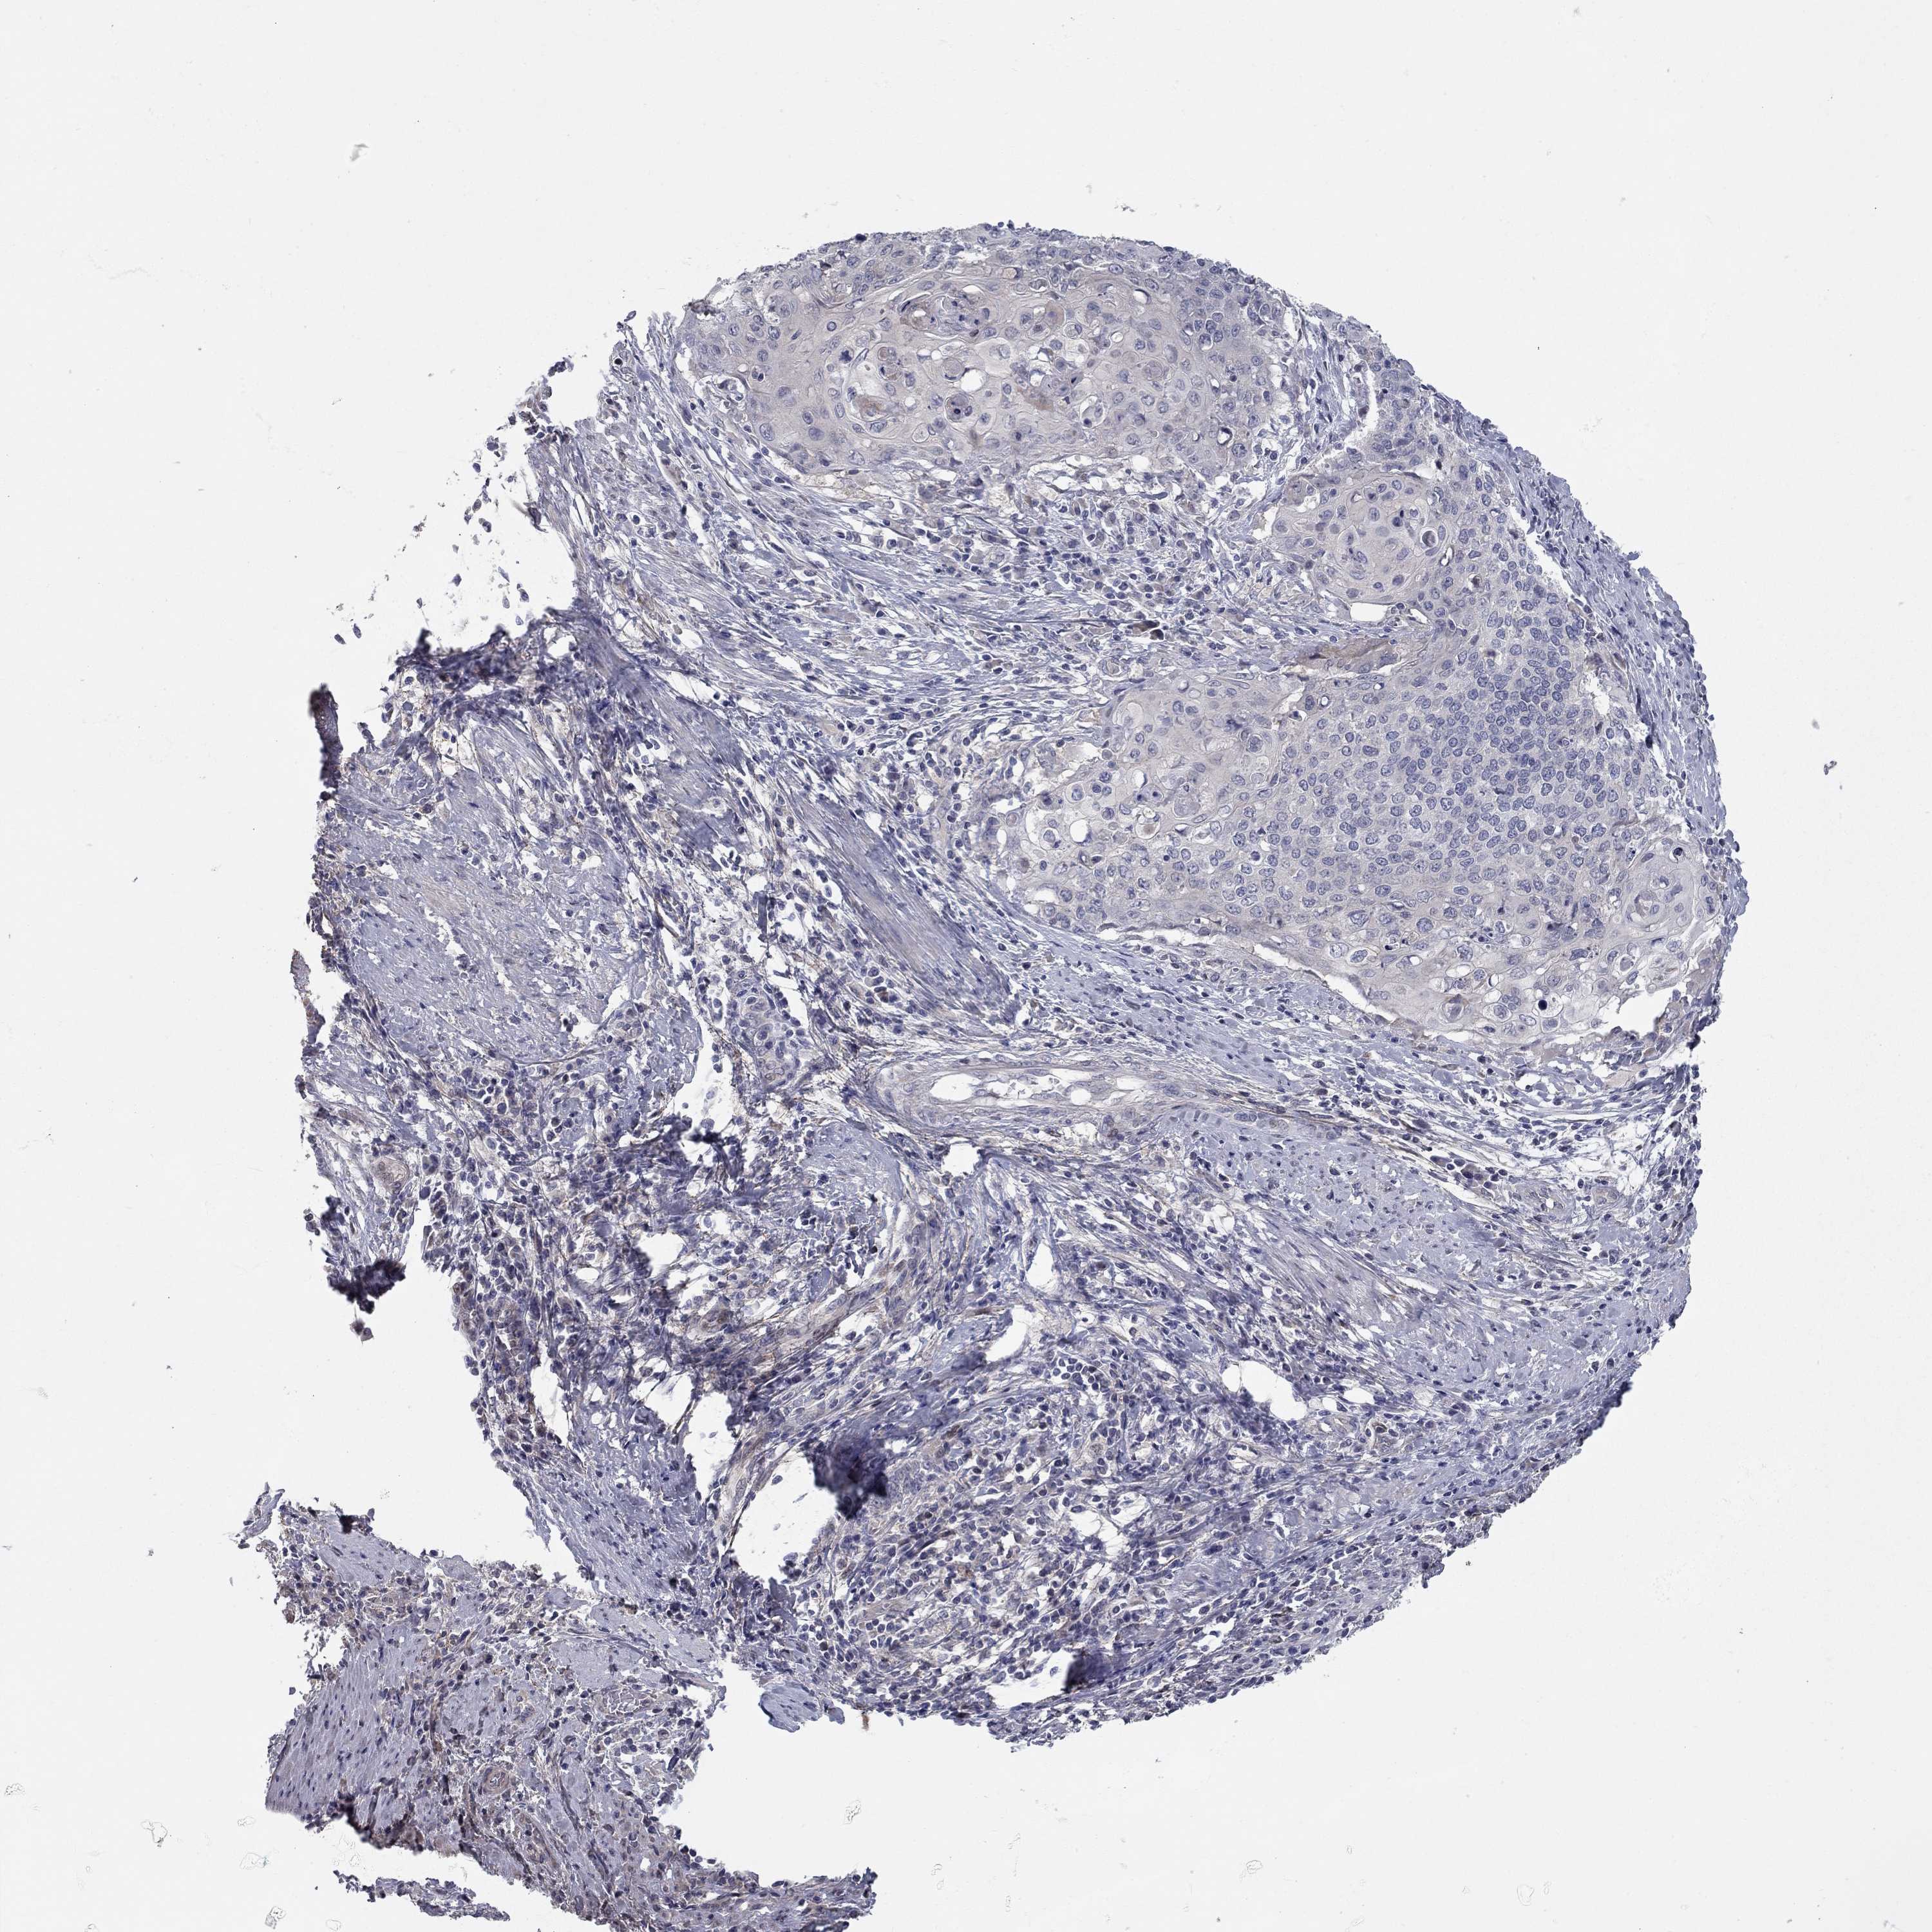

CERVICAL CANCER - Protein expressioni

A mouse-over function shows sample information and annotation data. Click on an image to view it in a full screen mode. Samples can be filtered based on level of antibody staining by selecting one or several of the following categories: high, medium, low and not detected. The assay and annotation is described here.

Note that samples used for immunohistochemistry by the Human Protein Atlas do not correspond to samples in the TCGA dataset.

Antibody stainingi

Antibody staining in the annotated cell types in the current human tissue is reported as not detected, low, medium, or high, based on conventional immunohistochemistry profiling in selected tissues. This score is based on the combination of the staining intensity and fraction of stained cells.

Each image is clickable and will lead to virtual microscopy that enables deeper exploration of all samples and also displays staining intensity scores, fraction scores and subcellular localization as well as patient and tissue information for each sample.

Antibody HPA073007

Staining

High

Medium

Low

Not detected

Intensity

Strong

Moderate

Weak

Negative

Quantity

>75%

75%-25%

<25%

None

Location

Nuclear

Cytoplasmic/membranous

Cytoplasmic/membranous,nuclear

Squamous cell carcinoma, NOS

Adenocarcinoma, NOS